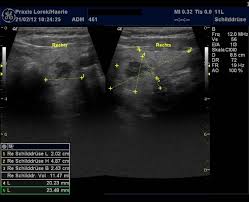

Arztpraxis Lorek Haerle Hashimoto Thyreoiditis Hypothyreose